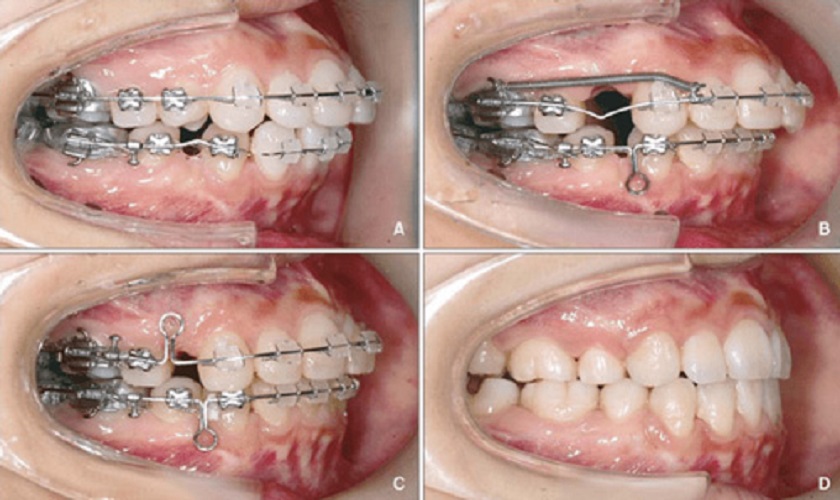

Trong tình huống răng mọc ngầm do quá trình mọc răng diễn ra chậm chạp, sự khuyết thiếu răng trên cung hàm, làm số lượng răng trên khuôn hàm không đầy đủ như bình thường thì niềng răng hay chỉnh nha để kéo răng ngầm ra ngoài là phương án tối ưu nhất.

Với phương án này, bác sĩ nha khoa sẽ tiến hành tiểu phẫu nhằm bộc lộ chiếc răng mọc ngầm dưới nướu, sau đó áp dụng kỹ thuật niềng răng với mục đích kéo chiếc răng ngầm ra khỏi xương hàm và đưa răng về lại vị trí thiếu răng trên cung hàm.

Biện pháp chỉnh nha kéo răng ngầm